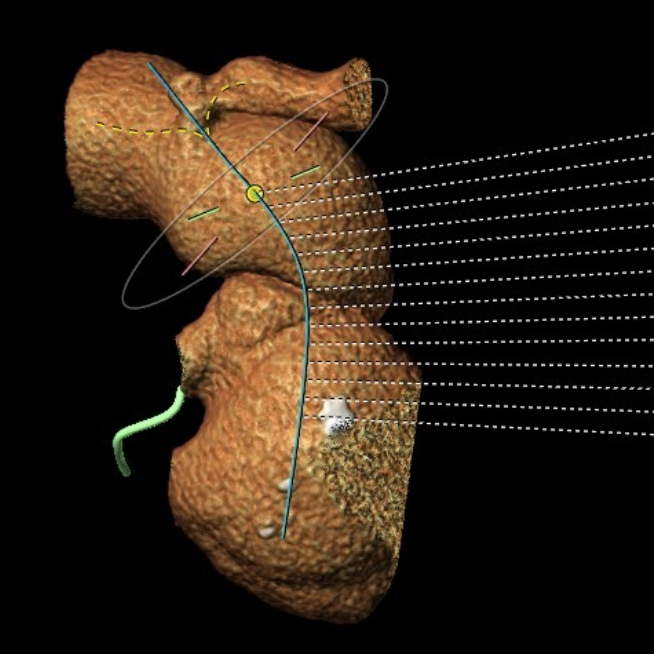

患者,男,32岁,入院超声提示为“肺动脉重度关闭不全并轻度狭窄,右心增大” ,术前影像学重建显示提示患者肺动脉干明显增宽,内径约38-45mm,瓣膜的固定成为了手术难点。经过术前多团队的缜密分析讨论,传统开胸手术建立体外循环对患者创伤大、手术操作复杂;该患者肺动脉明显扩张,经股静脉介入肺动脉瓣无法提供合适锚定位置;遂决定采用佰仁医疗Salus介入肺动脉瓣来解决这一问题,该瓣膜采用“哑铃状”镍钛合金记忆金属支架,优越的径向支撑力可锚定于病变部位,适用于可直接放瓣的肺动脉瓣反流/狭窄患者;通过独有的经胸介入方式,对于肺动脉解剖结构复杂、无法提供介入瓣膜合适锚定位置的患者,可同期行肺动脉成形术+介入肺动脉瓣植入术,达到理想的治疗效果,适用范围更广。

肺动脉形态